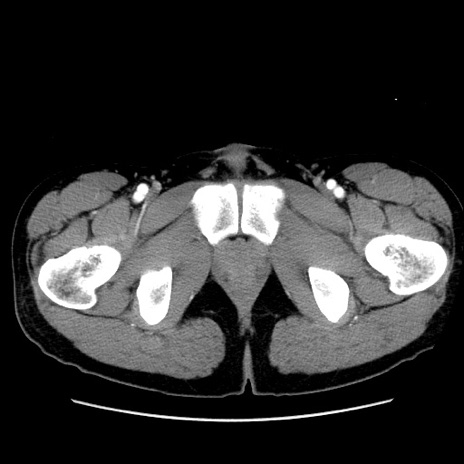

冠状断像

症例36(横断像)

【症例】20歳代 男性

【主訴】心窩部痛

【現病歴】今朝より上腹部痛あり。一旦軽快していたが再度出現したため救急要請。昨日夕に白身の魚を含む刺身を食べた。

【身体所見】BP 136/89mmHg、HR 74/min、BT 37.0℃、腹部:膨満、軟、心窩部に圧痛あり。反跳痛なし、筋性防御なし、腸雑音やや亢進あり。

【データ】WBC 17700、CRP 0.48